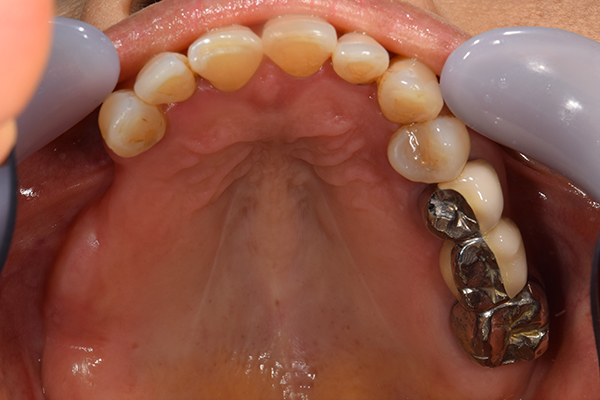

ケース5(金属使用 部分床義歯)

入れ歯をなくしてしまったので、あたらしく作りたい患者様です。

お口に入っている状態です。嘔吐反射が強かったため、うわあごの部分をくり抜いて作っています。

そのためにはしっかり歯に維持力をかける事、歯茎の部分に圧をかけるため、金属をつかって入れ歯を作成しました。

年齢 80代・女性

主訴 入れ歯をなくしたのであたらしくつくりたい。

治療期間 1ヶ月

治療費 義歯:330,000円(税込)

治療方針 以前作った入れ歯は気に入っていたが無くしてしまったとのことで、作り直しました。

上には残っている歯がありますが、入れ歯がない状態が続くと、歯へのダメージが強いことが考えられましたので、急ピッチで作っていくことにしました。

治療内容 入れ歯をつくるための前処置はとくに必要なかったため、すぐに入れ歯を作成していきます。

嘔吐反射が強く、普通の上顎の入れ歯を入れた時の違和感が強いため、口蓋部をくり抜いてつくっていきました。

そのため、歯や粘膜に維持負担を強くかけるため、金属を使用していくことにしました。

患者さんのお話をきいていると、前の入れ歯もそういう入れ歯をつくっていたとのことでした。

特記事項 入れ歯は完成してからがスタートです。入れ歯が歯ぐきにこすれて痛みが出る事が多いです。

今回の様な入れ歯ではそういう事が必ずと言っていいほどでます。

そのため、しっかり痛みをとるために入れ歯を調整して、患者さんに合わせた入れ歯にカスタマイズして完成になります。